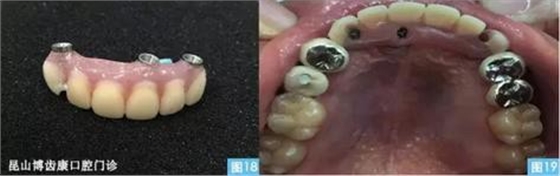

圖18圖19:臨時(shí)修復(fù)體及戴入口內(nèi)后的口內(nèi)照